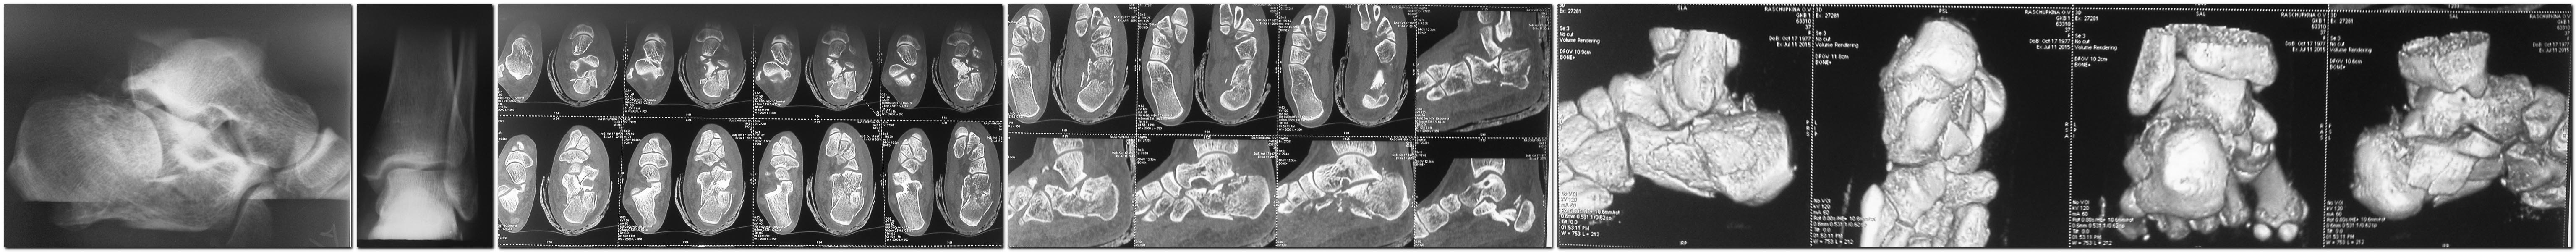

Во вложении фото снимков пациента на всех этапах лечения.

Определяем тип перелома:

1. К переломам I типа относим все краевые переломы, переломы с ротационным типом смещения (при этих переломах пользуемся рычаговыми способами репозиции: шилом, стержнями Шанца и т.д)

2. К переломам второго типа относим любой перелом при котором есть импрессия хотя бы одного фрагмента суставной поверхности. При этом типе перелома репозицию выполняем поэтапно: 1) Репозиция пяточного бугра по отношению к телу пяточной кости и фиксация аксиально спицей; 2) Дистракция для формирования пространства в подтаранном суставе для последеющей редукции осколков суставной поверхности; 3) Шилом с подошвенной поверхности стопы выполняем отверстие в направлении осколков суставной поверхности и толкателем произодим их репозицию снизу-вверх согласно их смещению. При этом каждый осколок репонируем отдельно (можно его временно фиксировать спицей к таранной кости). При необходимости возможны манипуляции шилом. В окончании репозиции восстанавливаем ширину пяточной кости сдавлением с боковых поверхностей руками или костными щипцами. При необходимости можно установить субхондрально винт (делаю это редко).

При репозиции осколки суставной поверхности часто сами правильно ориентируются о суставную поверхность таранной кости. Возможно управлять ими при помощи толкателя.